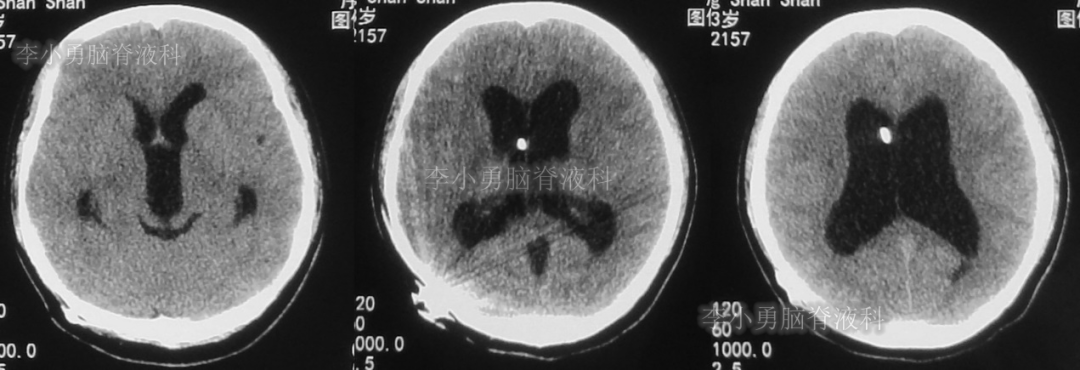

此后1个多月(2019年11月4日到2019年12月16日),患者意识一直无改善,一直呈模糊状态,多次复查头颅CT(图-12至图-20)见脑室大小反复变化不定,医生根据CT结果等反复多次调节分流泵压力(具体过程家属回忆不起)。但患者病情无好转却逐渐加重,逐渐不能咀嚼、吞咽及进食,卧床不起。

图-12:2019年11月8日头颅CT

图-13:2019年11月16日头颅CT

图-14:2019年11月19日头颅CT

图-15:2019年12月3日头颅CT

图-16:2019年12月10日头颅CT

图-17:2019年12月12日头颅CT

图-18:2019年12月13日头颅CT

图-19:2019年12月14日头颅CT

图-20:2019年12月16日头颅CT